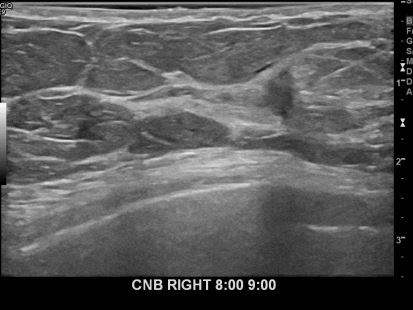

아산유외과개원후 657번째 유방암진단

상기환자 외부검사상 이상소견으로 내원하신 60대여성으로 우측에 의심스러운혹 조직검사시행해 유방암 진단되었습니다.